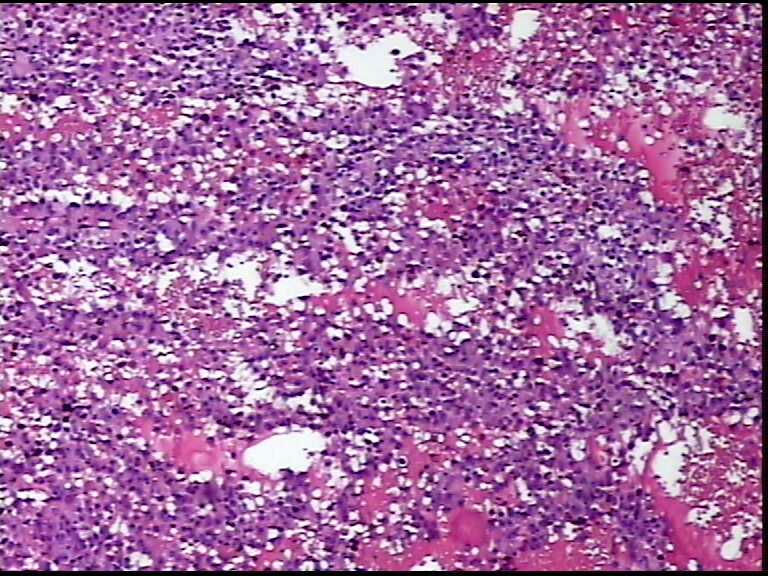

患者男性,34岁,临床没给提供,该患者梅毒阳性

• 请各位老师会诊一下 颌下淋巴结图2

图2

颌下淋巴结肿大,送检肿物直径2.5cm,切面灰粉色,质地嫩,先做了个LCA瘤细胞阴性

淋巴结内见大量宽而嗜酸性胞浆的肿瘤细胞,瘤细胞核大,偏心分布,核仁明显,成上皮样表现,部分似有腺泡样排列,符合淋巴结转移性恶性肿瘤,首先除外转移癌,恶性黑色素瘤,继而除外浆细胞瘤(岁数不太符合),横纹肌肿瘤等。

淋巴结内见大量宽而嗜酸性胞浆的肿瘤细胞,瘤细胞核大,偏心分布,核仁明显,成上皮样表现,部分似有腺泡样排列,符合淋巴结转移性恶性肿瘤,首先除外转移癌,恶性黑色素瘤,继而除外浆细胞瘤(岁数不太符合),横纹肌肿瘤等。同意楼上的观点。